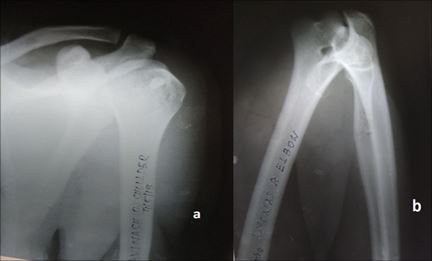

AN UNUSUAL CASE OF IPSILATERAL SHOULDER AND ELBOW DISLOCATION

A 34 years old male, labourer by occupation was brought to our trauma centre in an inebriated state with a history of fall from a height of approximately 10 feet. He complained of pain in the right elbow. A complete examination of the affected upper limb revealed an ipsilateral anterior shoulder dislocation and a posterior elbow dislocation with no other concomitant injuries. Both the dislocations were reduced conservatively and the patient was successfully managed. The patient is absolutely fine now, 6 months post his dislocation and has resumed back to his work. This case has been presented to highlight the rare and unusual nature of the injury, since ipsilateral dislocation of shoulder and elbow occur infrequently.